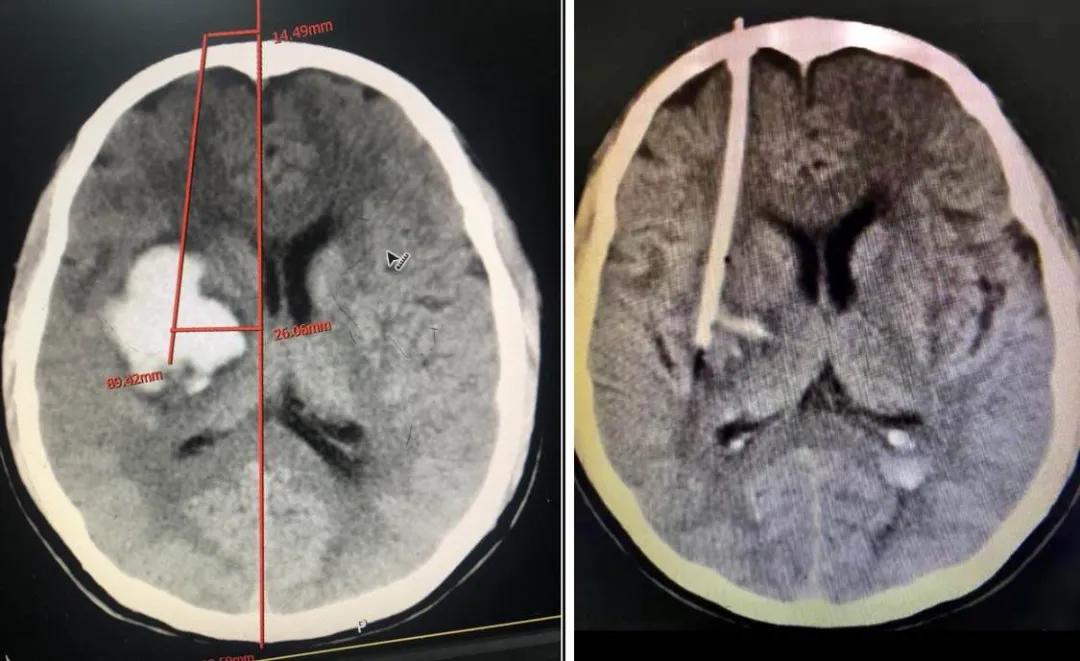

患者林某,男性,82岁,反复头晕半个月,症状时好时坏,未引起重视,未进行治疗,4月27日突发右侧肢体无力,无不能言语,无人事不省,无口吐白沫、双眼上吊、四肢抽搐,无大、小便*禁失**。经查,该患者左侧额、颞、顶部亚急性硬膜下血肿,右侧顶部硬膜下少量出血未除。左侧额颞顶部硬膜下血肿清除术后,于2020.04.28在全身麻醉下行“内镜下颅内血肿清除术+脑积液漏修补术+颅骨修补术”。

术后降低颅内压及抗感染治疗,患者状态良好,病情得到恢复。

术前

术后